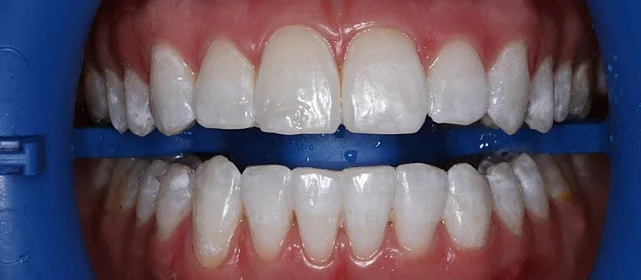

Обратилась с жалобой на скученность верхней и нижней челюсти средней степени тяжести — рецидив после подросткового лечения (ретейнер не носила).

Результат

полное выравнивание зубных рядов без удаления зубов. Рецессия десны не прогрессировала (контроль по КТ через 12 месяцев). Пациентка носит несъёмные ретейнеры

и ночные капы.